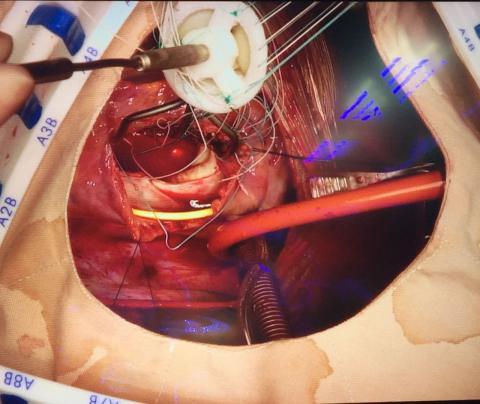

Surgeon - Cardiothoracic

Coronary artery by pass

Valve repair/replacement

• Cardiac

• Coronary disease

• Valve disease